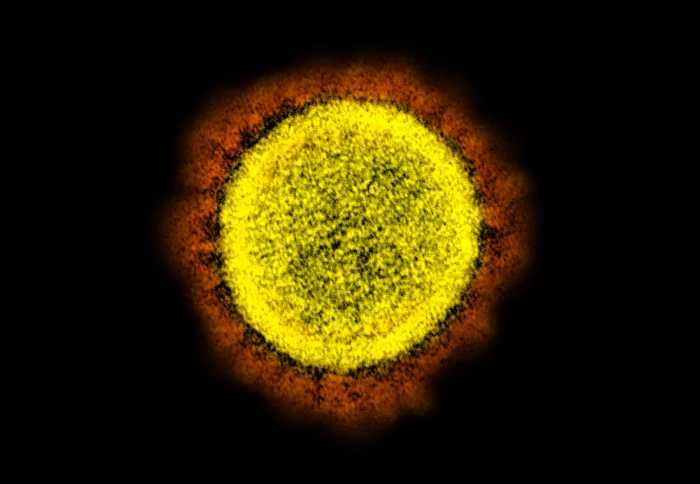

Compounds which bind to the spike protein block antibodies from neutralising SARS-CoV-2

In the study, researchers at the Crick were involved in the development of tests that see if a person has been exposed to the virus, and discovered that the SARS-CoV-2 spike protein strongly binds to biliverdin, giving the proteins an unusual green colouration.